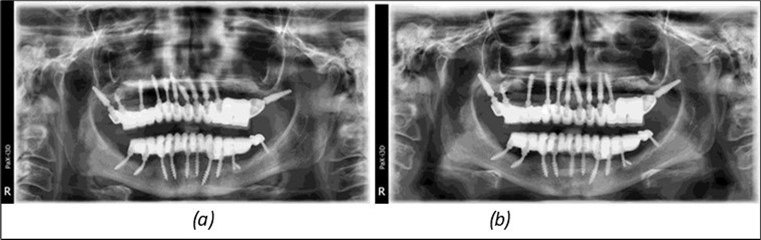

Figure 14.Rx panoramic final situation control: (a) Panoramic X-ray with the addition of a distal BCS implant in quadrant 3 at 11.2022; (b) Control X-ray, 10.2023.